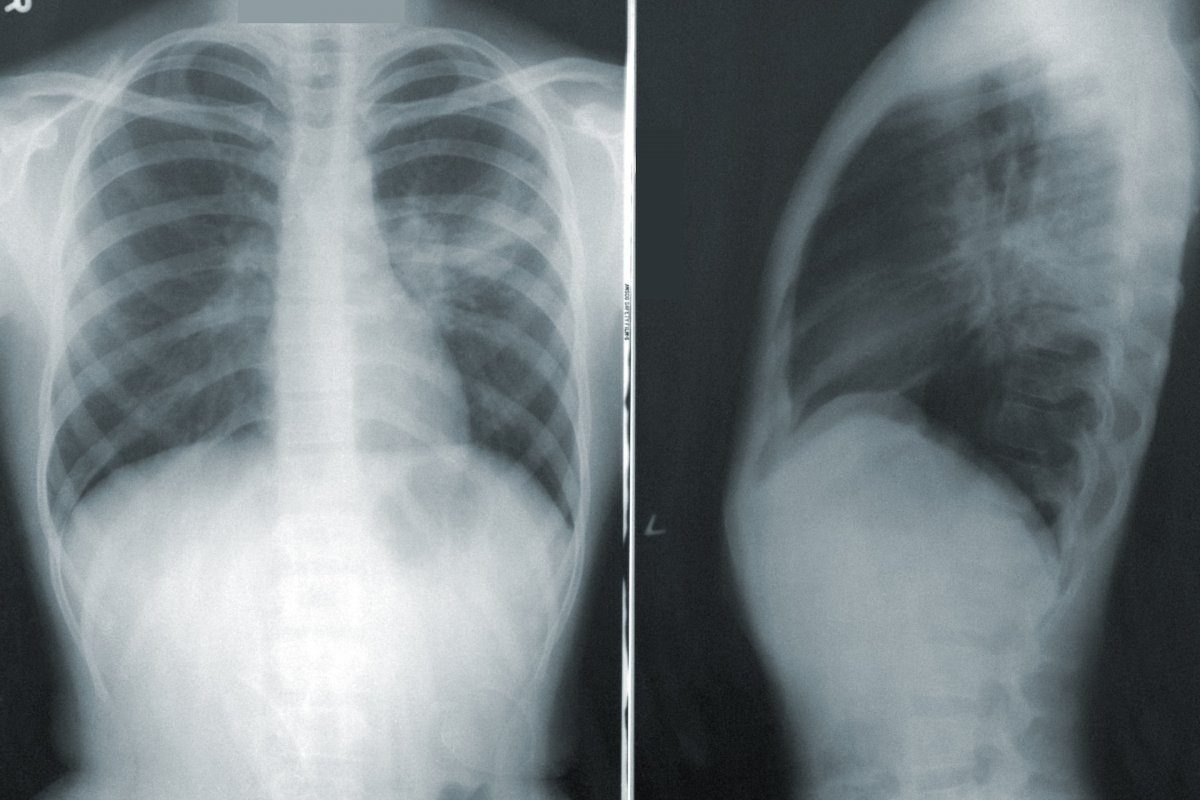

Imaging Studies: X-rays and Advanced Techniques

Imaging is key to confirming pneumonia and seeing how bad it is. Chest X-rays are the first step, showing lung damage. Sometimes, advanced imaging techniques like CT scans are needed for more details.

We use physical checks, lab tests, and imaging to accurately diagnose pneumonia. This helps us tell if it’s viral or bacterial, so we can treat it correctly.